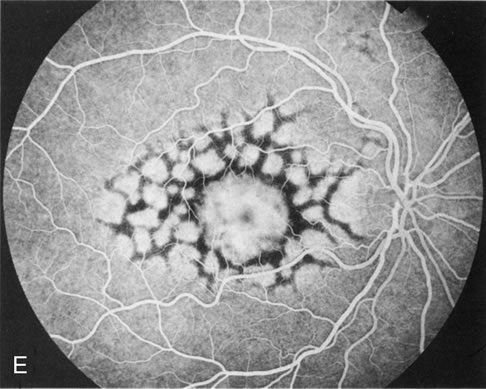

Reticular dystrophy

This dystrophy is characterized by a network of hyperpigmentation, resembling a fishing net with knots, located in the RPE and a presumed unaffected choriocapillaris. [30] The network of hyperpigmentation extends 4 to 5 disc diameters from the macula in all directions. Each net of meshes is typically 1 disc diameter or less. The midperiphery and periphery are unaffected early in the disease process. With age, most lesions fade away. However, some are replaced with atrophic changes in the RPE.[5] In the advanced stages, the network becomes bleached and irregular with small white dots appearing in the RPE.[28]

Fluorescein angiography demonstrates a mosaic pattern, showing hypofluorescent bands or segments surrounded by areas of non-leaking hyperfluorescence. This corresponds to the reticular bands of pigment epithelial hyperpigmentation surrounded by halos of hypopigmentation as seen with the ophthalmoscope. The choroidal vessels appear to be normal.